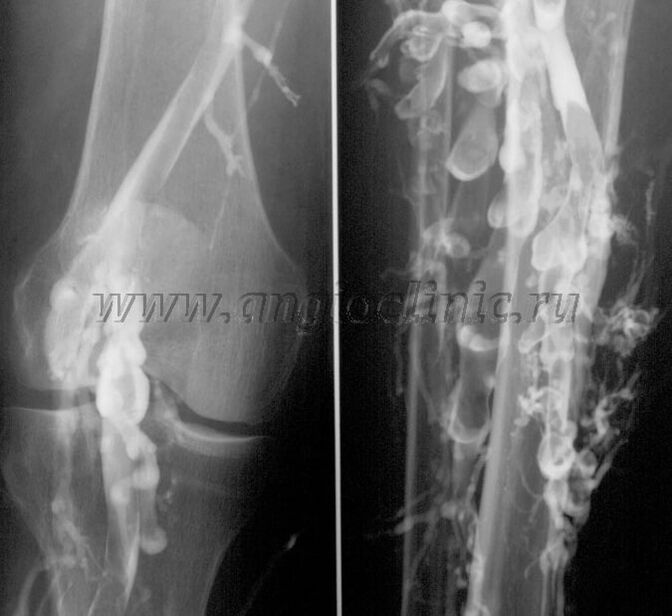

Contrast venography

Usually, ultrasound examination is sufficient for the complete diagnosis of venous pathology, but in some cases it is necessary to study the relationship between the state of the deep and superficial venous system, especially in the case of relapses of varicose veins and secondary varicose veins.

Contrast X-ray examination is used to solve these problems.The saphenous veins are punctured and contrast is given.The movement of the contrast is observed on the monitor of the X-ray machine, and all necessary tests and predictions are made.Currently, venography is used very rarely for varicose veins.